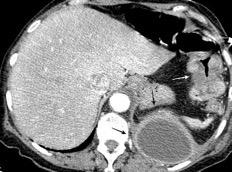

Marzo 2014: Perforación longitudinal distal secundaria a episodio de vómito (síndrome de Boerhaave). Derrame pleural izdo. que evoluciona a empiema.